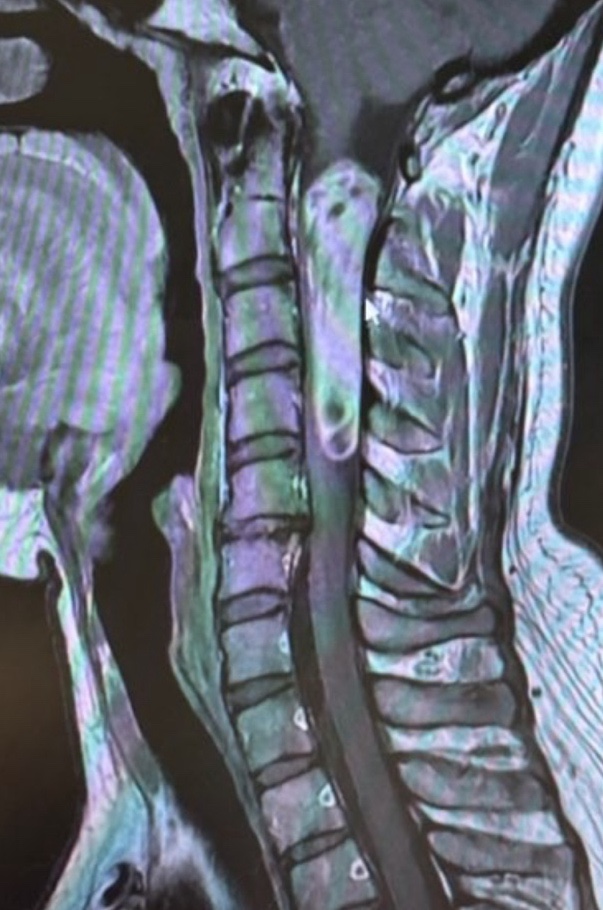

아프다 못해 위험한 일도 생기고 하여 더이상 미룰 수 없어 정형외과 방문. 내 병에 대해 알게 되었다. 천...

천안 민상혁기둥정형외과 진료후기/척수종양/양성척수종양/경추종양/경막내수내/1

진료후기-서울대병원-/척수종양/양성척수종양/경추종양/경막내수내종양/3

종로 서울대 본원 ㄱㅊㅎ교수님 09:45 예약 이번에는 열차 이용해봄 06:05출발 07:05ktx 출발 48도착 08:35...